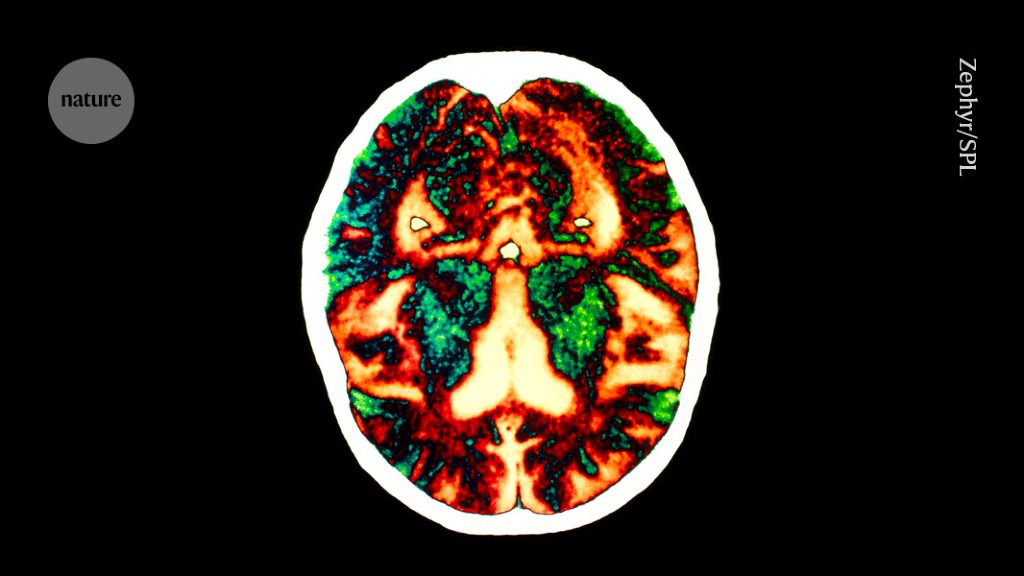

A study suggests that sticky proteins linked to Alzheimer's disease may have been transmitted through cadaver-derived growth hormone treatments, leading to signs of early-onset dementia in some recipients. The research, based on a small number of cases, indicates that amyloid-beta proteins present in the hormone preparations may have caused brain damage. While the study has limitations and the findings are not conclusive, it raises questions about the potential transmissibility of Alzheimer's disease through biological material. However, experts caution that the study's small size and the presence of other medical conditions in the recipients make it difficult to draw definitive conclusions, and emphasize that there is currently no need for public concern regarding transmissible dementia.